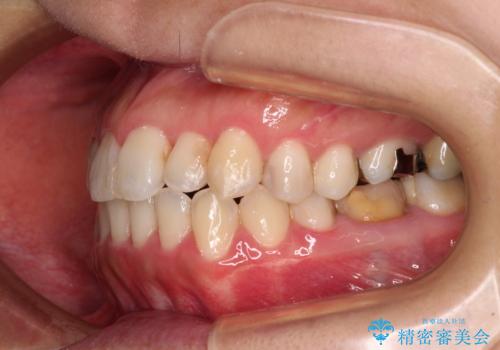

- 前歯の捻れを気にして来院された患者様です。

上顎前歯が捻れて前方に飛び出しており、下顎前歯もそれに沿うようにデコボコとなっていました。

IPR(歯と歯の間を削る処置)によりスペースを獲得して上下前歯のデコボコを改善し、インビザラインにて矯正治療を行うこととしました。

捻れていた前歯の形態が、先端が欠けていたり、一部むし歯処置により左右非対称の形態となっていたため、なかなかゴールが定まらず、治療期間がかかってしまいました。